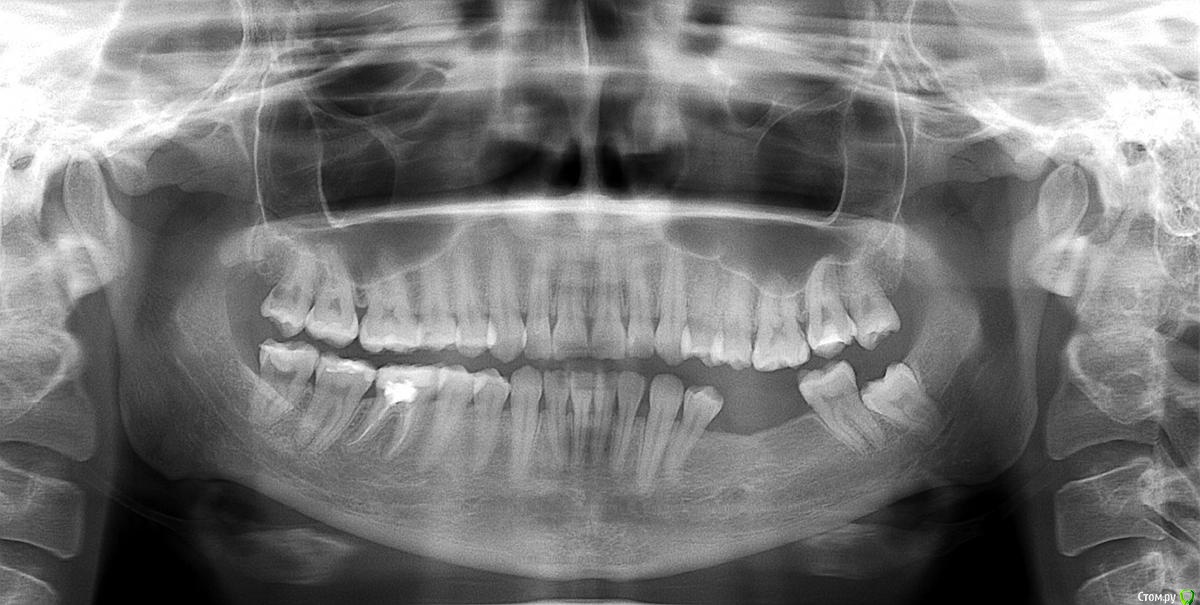

korolewwna Опубликовано 20 января, 2020 Поделиться Опубликовано 20 января, 2020 Здравствуйте, у меня на 18 и 48 зубе диагноз предположительно пульпит. Пришеечный кариес у обоих. Зубы со всех сторон черные и на каждом есть полости. 48 зуб уже 2 раза лечили. 18 зуб повернут жевательной стороной в щеку, мне ни один стоматолог не предлагал его лечить, так и доходилась с ним до пульпита. Была на приеме у нового стоматолога, он предложил мне все таки полечить мне 18 зуб и 48 соответственно или оба удалять. Подскажите пожалуйста, стоит ли мне лечить зубы мудрости или оба удалять? 48 зуб уже стал немного реагировать, 18 пока не беспокоит. Ссылка на комментарий